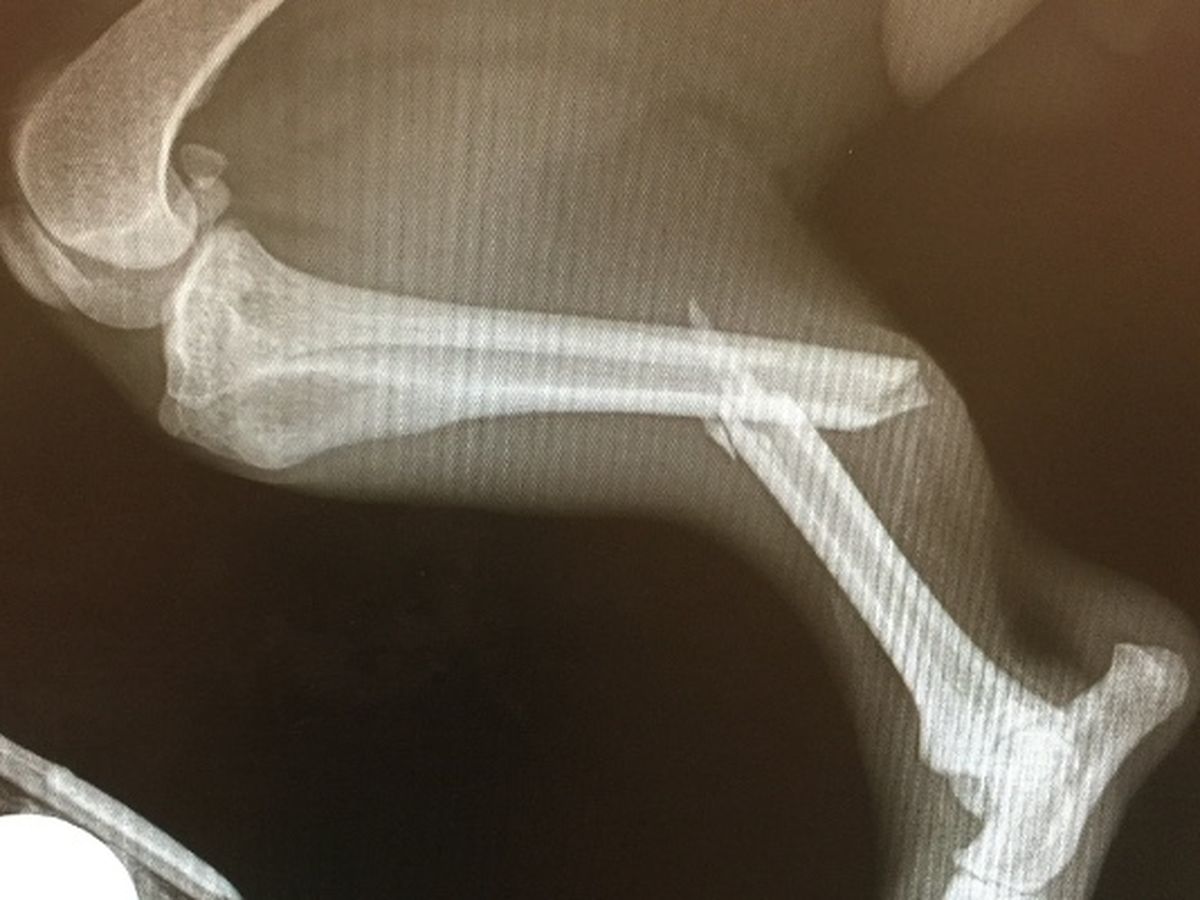

My husband and son quickly got in the car to chase him as he is really fast. Unfortunately, Chase decided to run onto a busy street and ran into the back of a vehicle breaking his leg. He still did not want to be caught and continued running until my son was finally able to catch up to him. They noticed right away that his back right leg was flopping around. They called me as I was away from home and I came home as quick as I could.

Of course this happened on a Saturday afternoon and our normal vet we see is closed. I took him to a local ER veterinarian to X-ray his back leg to see how bad it is. Chase was in shock and they put him on IV fluids and medicine to help calm him down, treat his pain and to finish assessing him.

After taking the X-ray, we discovered he snapped his back right leg in half. The ER vet quoted me $3000 to $4000 to have surgery to fix his break during the week when they had more staff on hand. They would charge around $1500 to $2000 to amputate his back leg if we chose to go that route. She told me low income veterinary offices might charge close to $700 to amputate and I might want to call around on Monday to see what I can find if I chose for them to not operate on Chase.